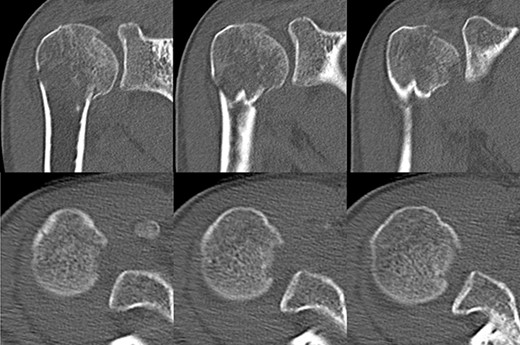

A 39-year-old man was transported via ambulance after being hit by a car. The radiographs revealed a one-part proximal humeral fracture with displacement at the surgical neck (Fig. 1). However, computed tomography (CT) revealed humeral head impression fracture and lesser tuberosity fracture in addition to a surgical neck fracture (Fig. 2). In addition, 3D-CT revealed that the collapse occupied approximately 20% of the articular surface with no glenoid defect (Fig. 3). Therefore, we first performed arthroscopic-assisted reduction and internal fixation of the humeral head impression fracture, followed by open reduction and internal fixation (ORIF) of the proximal humeral fracture.

3D-CT scan showing approximately 20% of articular surface of the right proximal and no glenoid defect, indicating no posterior shoulder dislocation.